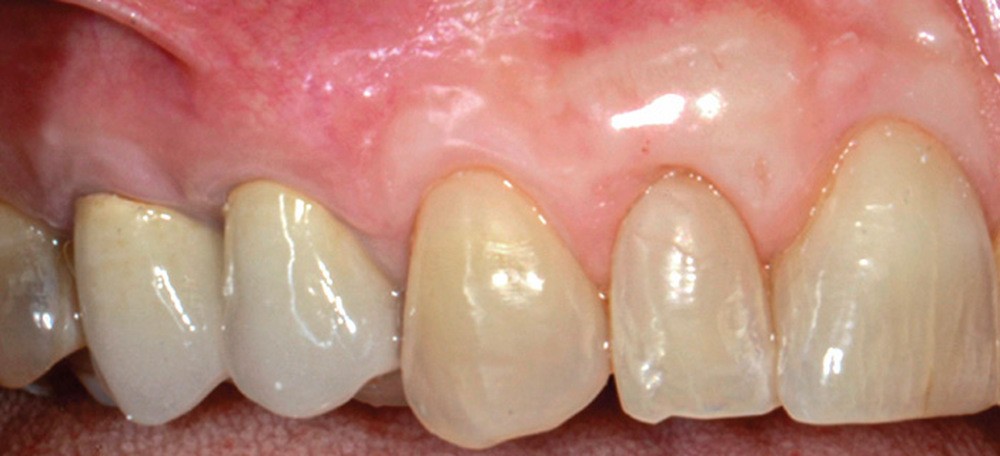

Cette technique, sans greffon de conjonctif associé, permet un taux de recouvrement complet de 80 %. La préservation de l’épaisseur du lambeau et la présence du périoste semble jouer un rôle fondamental dans l’obtention du recouvrement complet.